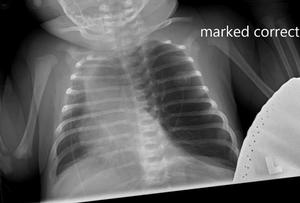

On physical examination, the patient appeared to be in significant respiratory distress. Her oxygen saturation was 96% on high-flow nasal cannula.